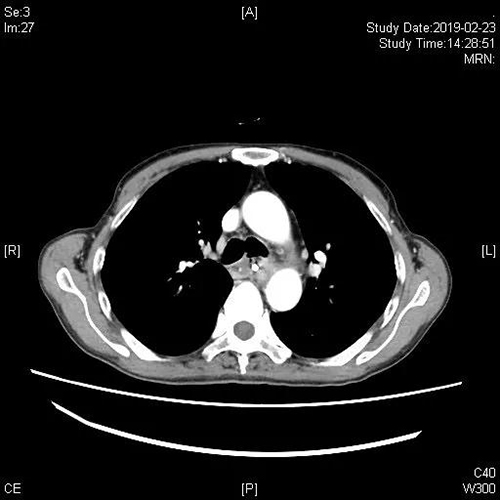

治疗前CT:A瘘口

B肺部感染

患者经硬镜下“Y”型覆膜支架顺利封堵瘘口并充分吸痰,积极抗感染治疗后,患者体温得到有效控制,复查胸部CT炎症明显好转,可自主进食,解决了患者长期以来无法进食及肺部感染的问题,生活质量得到极大提高。患者及家属对治疗效果非常满意。